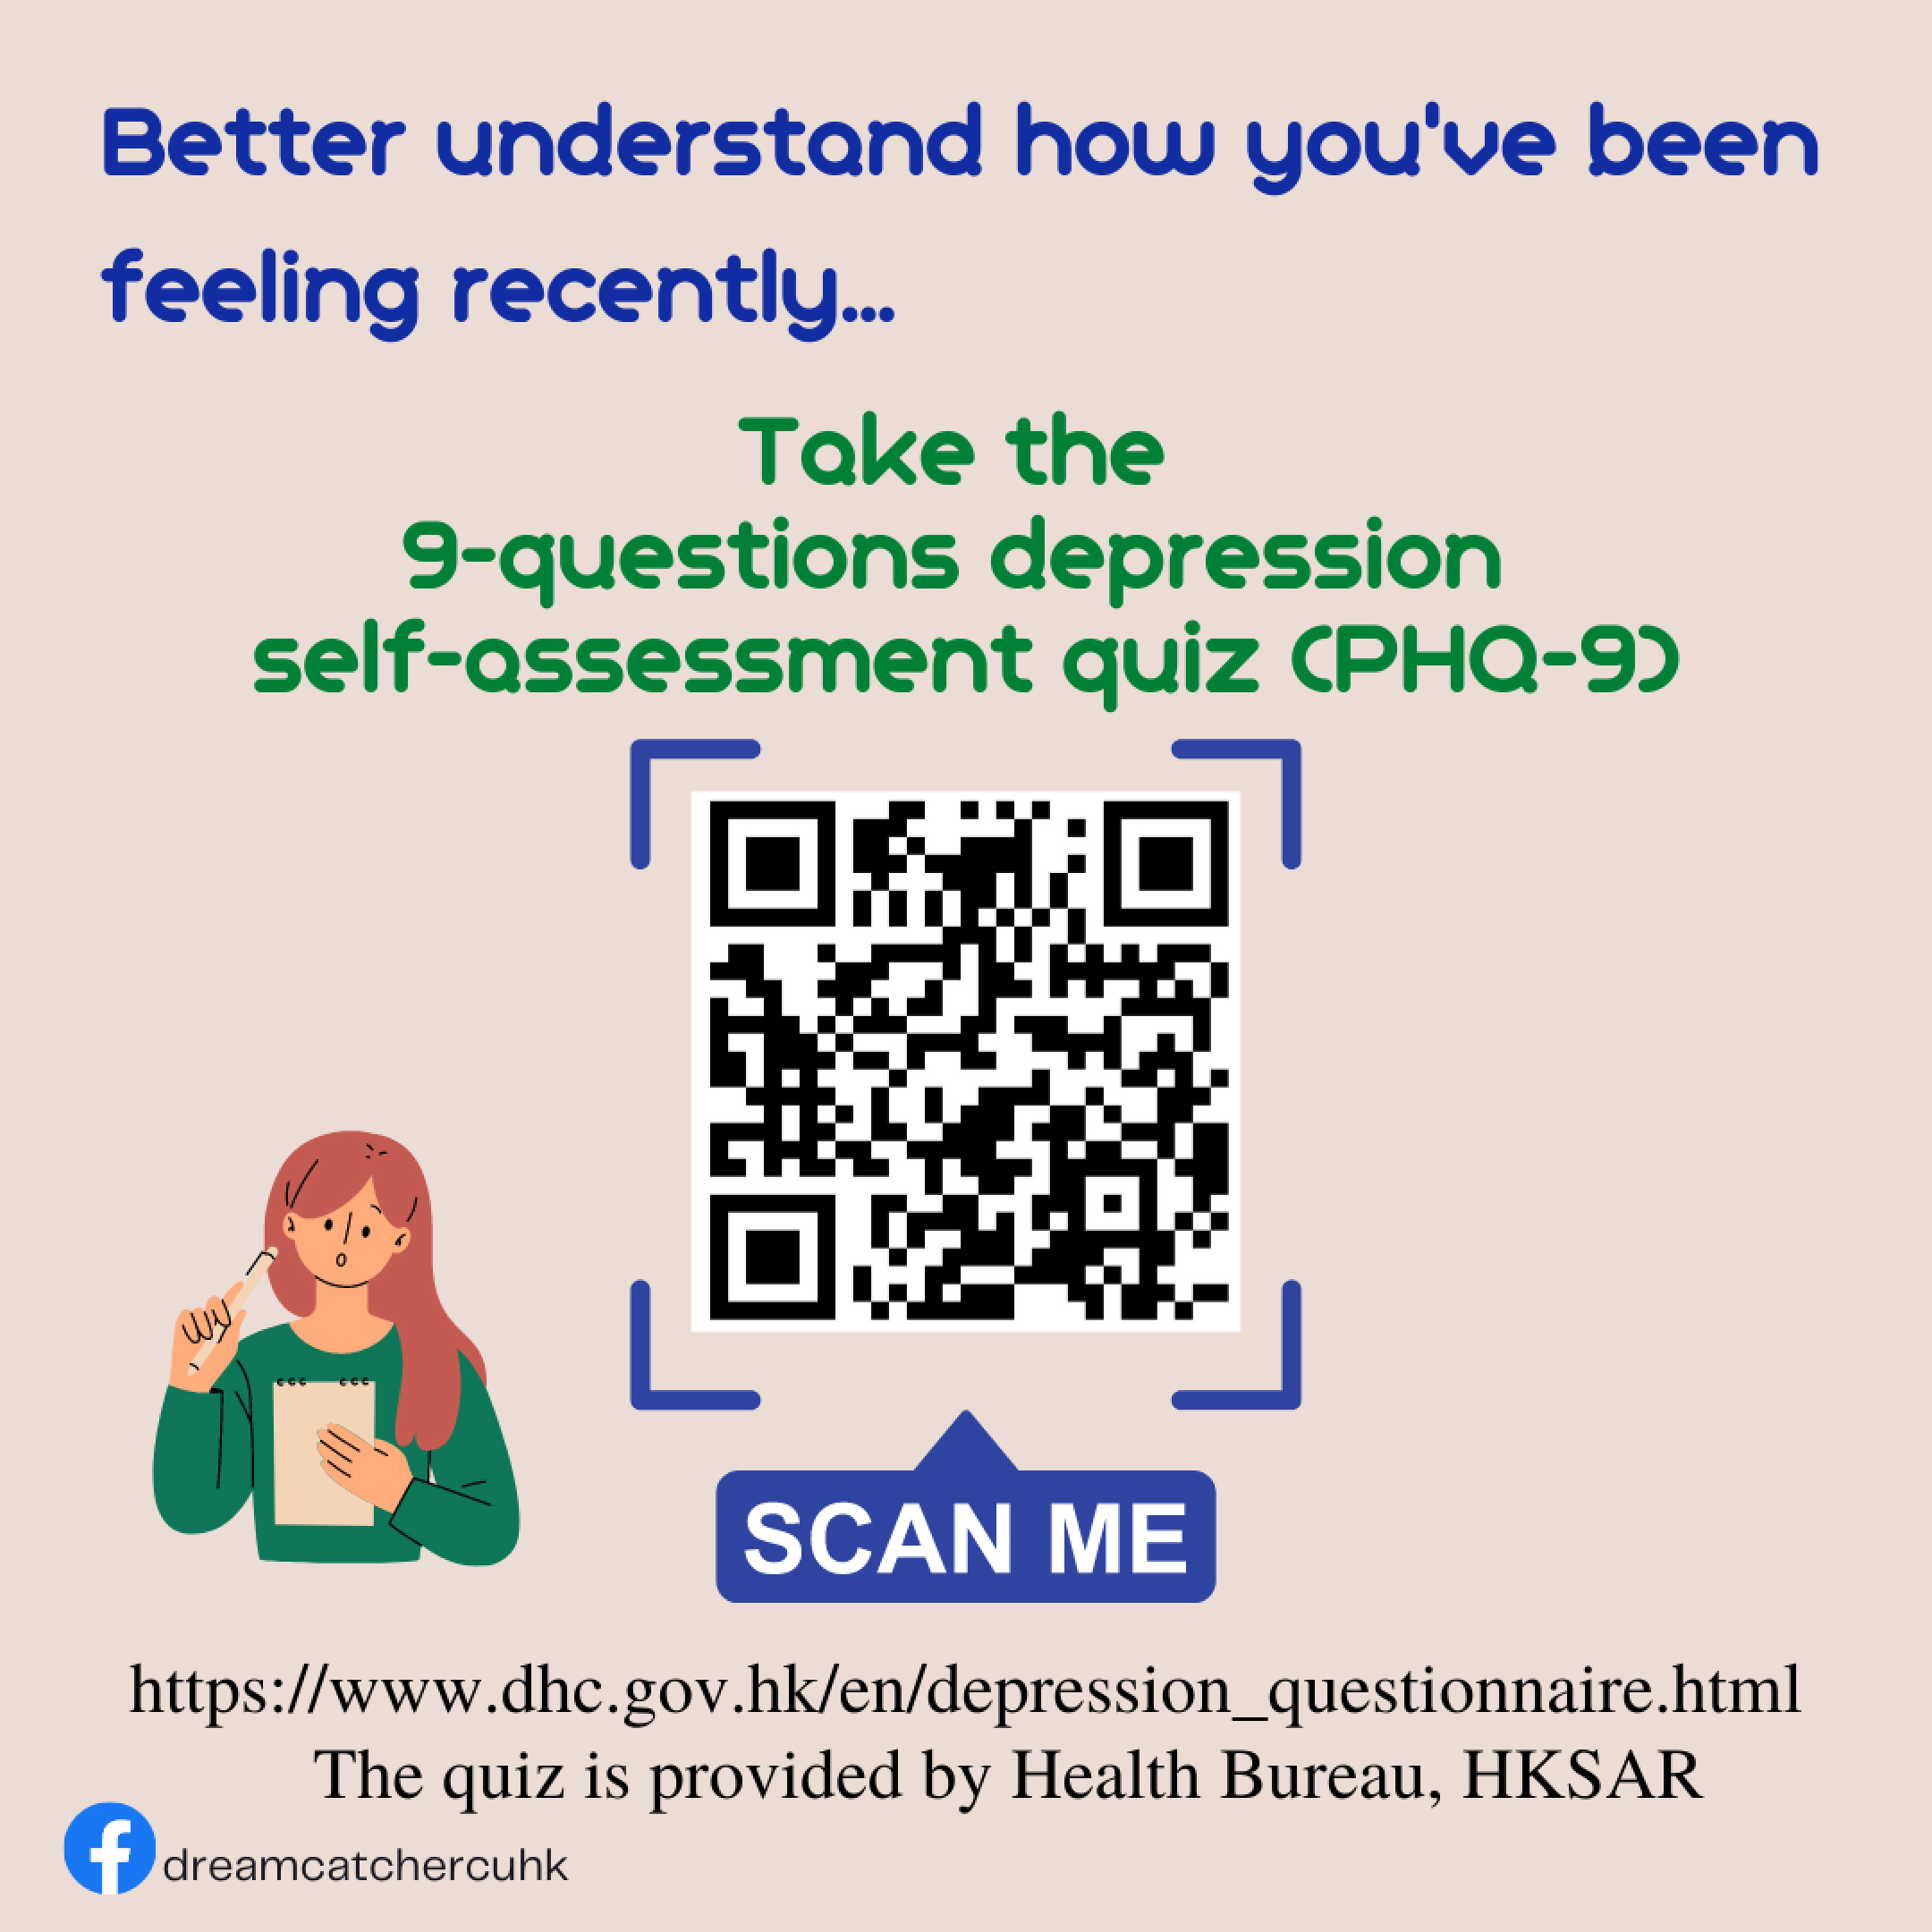

Resources and Activities